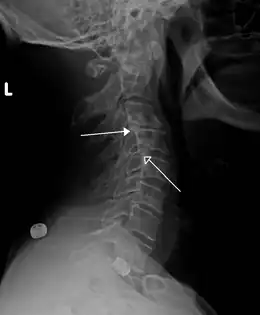

Rétrolisthèses de stade 1 de C3 sur C4 et de C4 sur C5

L'importance du glissement se mesure en prenant une radiographie (de profil). Un rétrolisthésis, dans ses cas les plus graves (lorsqu'il comprime la moelle épinière ou une racine nerveuse) peut entraîner une paralysie partielle (hémiplégie) ou totale (tétraplégie).